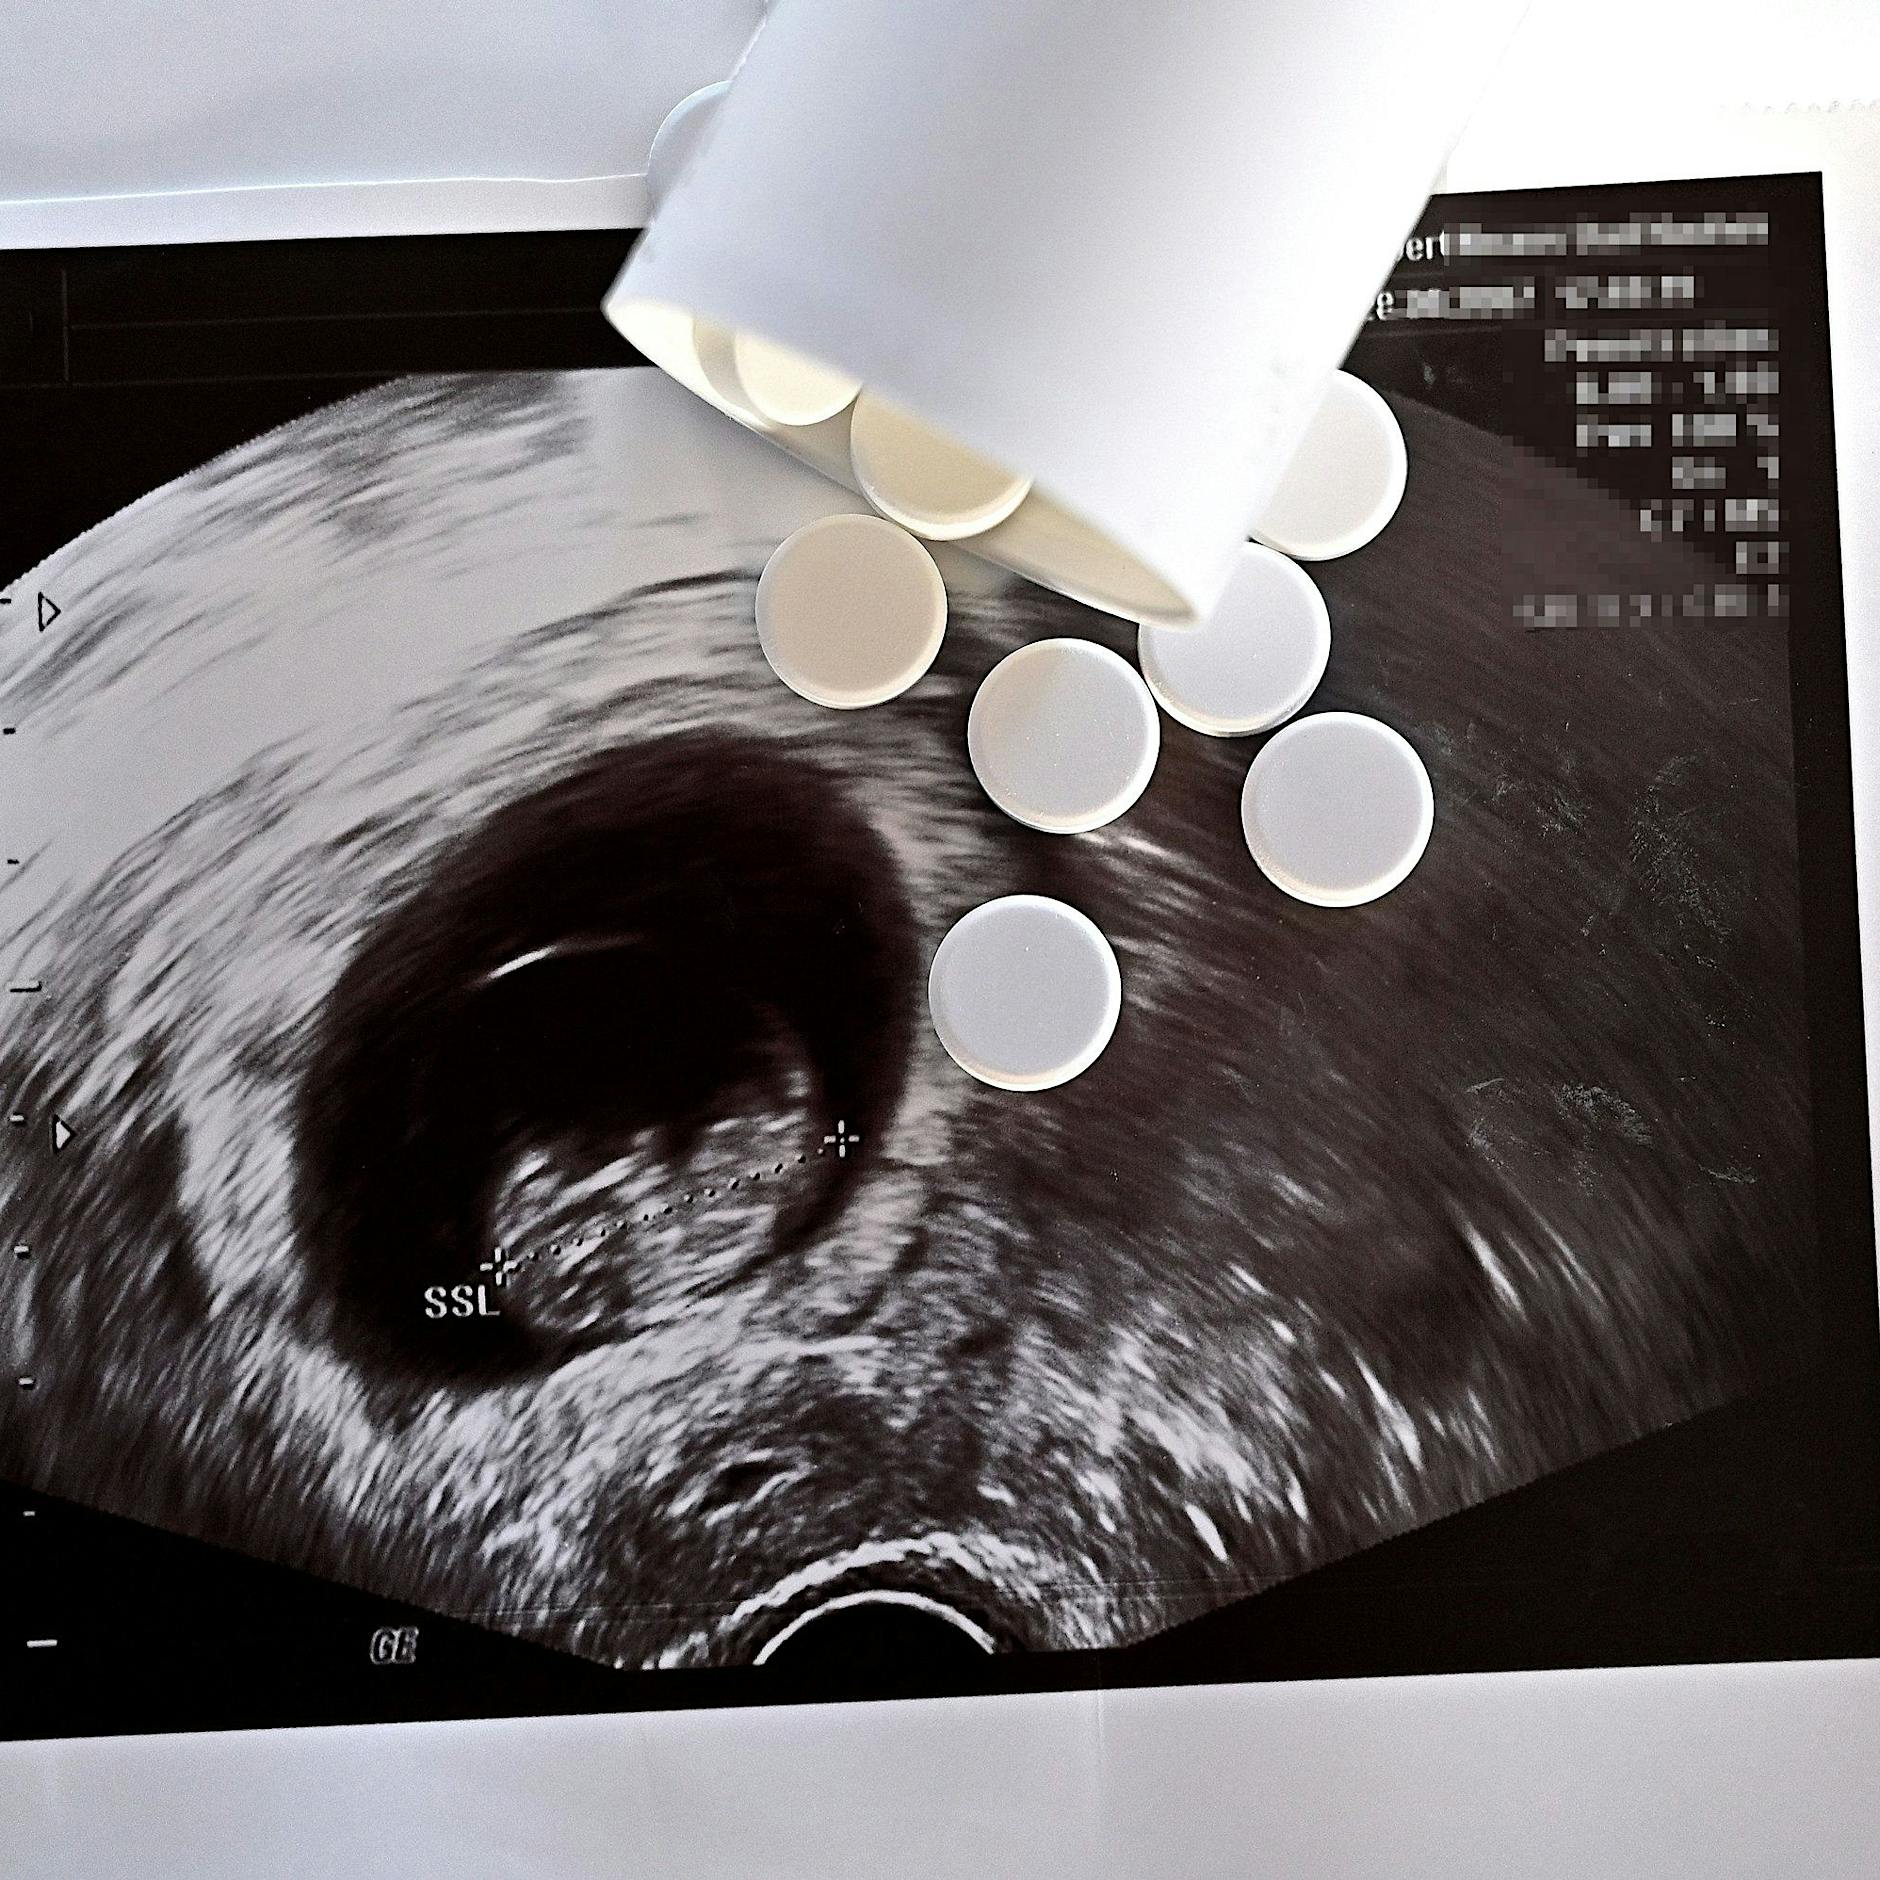

Bisweilen organisiert „Tante Barbara“ auch ungewöhnliche Hilfsaktionen: So flog im Juni 2015 eine Drohne mit zwei Packungen mit Abtreibungspillen von Frankfurt (Oder) nach Slubice – der Grenzschutz konnten sie nicht aufhalten. Das war aber eher als PR-Aktion geplant.

Die Soziologin Elzbieta Korolczuk, die in Warschau unter anderem zu Frauenbewegungen forscht, merkt an, dass die meisten Abtreibungen in Polen durch Medikamente vorzeitig beendet werden. „Abtreibungstabletten sind effizienter“, sagt sie, „und beliebter.“

Wenn der Fötus unheilbar erkrankt ist, ist in Polen eine Abtreibung neuerdings illegal. Die Geschäftsstelle von Pro Familia e.V. in Frankfurt (Oder) teilt indes schriftlich mit, dass keine Presseanfragen beantwortet werden.